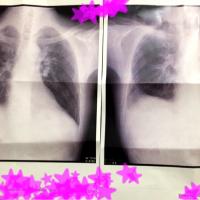

フォロー ブログを報告 登録ID 1841555 タイトル おかっちの白血病から生き直し。びわ王子 URL http://s.ameblo.jp/biwanohaya?frm_id=v.jpameblo&device_id=e9d63d1ec2504f4398b02d581aa47004 カテゴリ がん・腫瘍 (139位/453人中) 闘病記 (106位/258人中) 代替療法 (36位/126人中) 悪性リンパ腫 (9位/37人中) 玄米菜食 (7位/12人中) 紹介文 H27.11/13.Tリンパ芽球性リンパ腫/白血病発症。H28.4/?骨髄移植。H28.9/24退院。H28.12/26肺炎。H29.2/20胸腰椎圧迫骨折。 登録:2016年05月(9年) 2 記事一覧